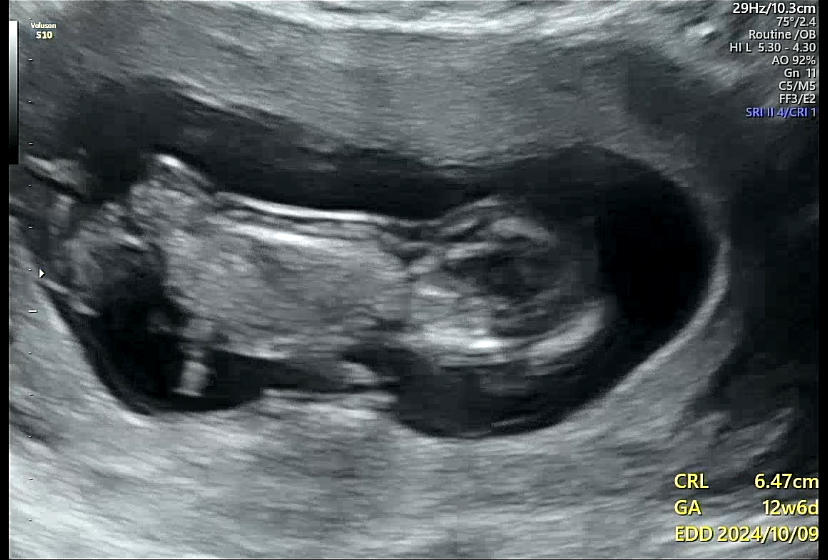

8주 검진 이후로 지난한 4주를 지나 12주차가 되었다. 오랜만에 보러가는 딱붕이와 긴장되는 1차 기형아 검사.

처음으로 배 초음파를 했다. 너무 좋았음! 질 초음파는 힘드로...

배 초음파를 하는데 태아가 꿈틀꿈틀 열심히도 움직였다. 백숙같은 몸매를 뽐내는 딱붕스

1차 기형아 검사의 포인트!

목투명대의 두께와 콧대의 유무이다.

태아가 너무 움직여서 심장소리와 목 투명대 길이를 재는데 애를 먹었다. 초음파를 보면서 귀엽다는 생각이 드는 나는 엄마가 되어가는 건가...!

목 투명대는 1.46mm가 나와서 정상이라고 하셨다. 1~3mm 사이면 정상 범위이고 3mm이상부터는 다운증후군 고위험군으로 판단된다. 그런데 2.5mm 대 정도도 걱정스러운 정도라서 좀 더 정확한 검사인 니프티 검사를 해보자고 하기도 한다.

콧대가 없으면 안면장애나 다운증후군이 의심되는데 콧대도 발견되었다!

출혈도 안보이고 아이도 건강하게 있는 걸 보고는 의사선생님이 "다행히 자리를 잘 잡았네요. 건강하게 잘 자라고 있습니다. 이제부터 안정기입니다" 라고 하는 말에 어찌나 마음이 놓이던지...ㅠ 의사쌤이 별 말을 안하셔서 몰랐는데 걱정 시키지 않게 하시려고 했다는게 느껴지는 검진이었다... 감사해요ㅠㅠ

(성별은 알 수 없었다. 태아가 별다른 힌트를 보여주지 않았음)